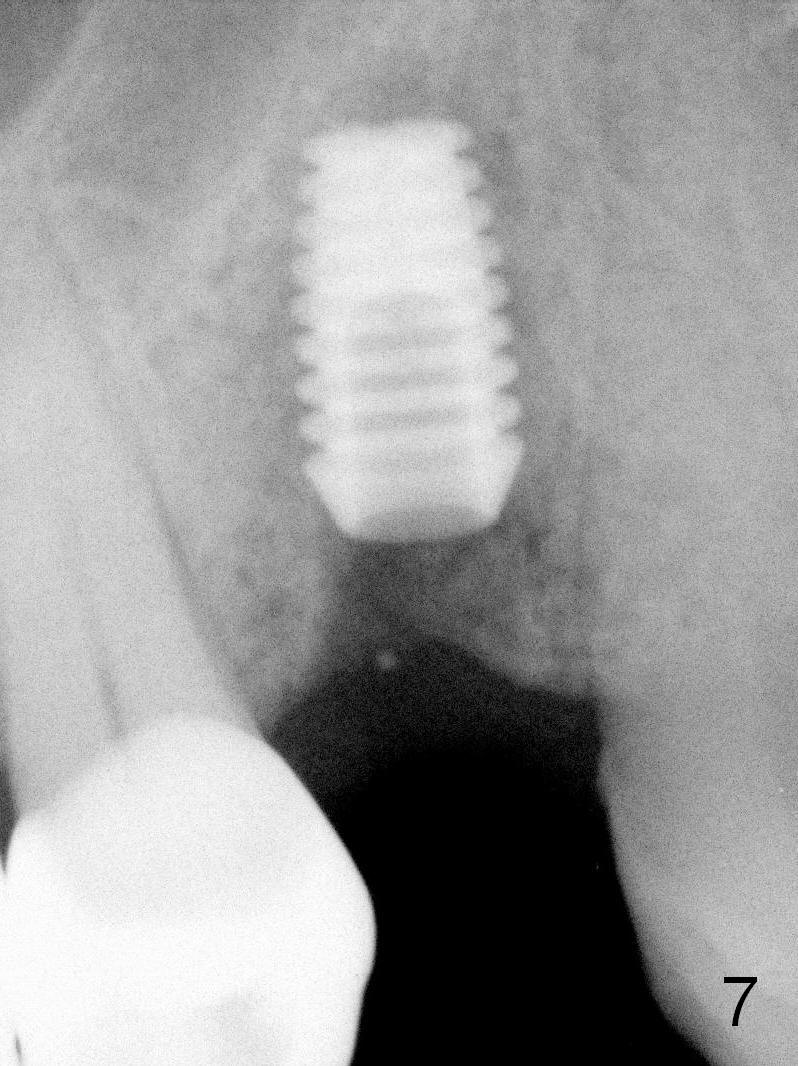

A 68-year-old man has pain and swelling associated with the tooth #5 (Fig.1). The fistula (*) is connected to the periapical radiolucency using a gutta percha (Fig.2 <). There are deep pockets distobuccal and lingual. The lingual root is found to have oblique fracture upon extraction. The distobuccal plate perforates (Fig.3). Collagen plug is placed. The buccal plate is concave (Fig.4) and socket density is low 2.5 months post extraction. Three months post extraction a 4.5x8 mm Bicon implant is placed after reamer and osteotome osteotomy (Fig.6). Bone density around the implant appears to increase 5 months post placement (Fig.7). Porcelain-fused-to-metal crown is cemented 2 weeks later. Bucco-occlusal porcelain chips 2 months post cementation. The patient decides to redo the crown. PA is taken before crown removal (Fig.8: 3 year 10 months post cementation). When a straight abutment is removed (Fig.9 A), a 15° angled abutment has to be used (Fig.10 red) for restoration.